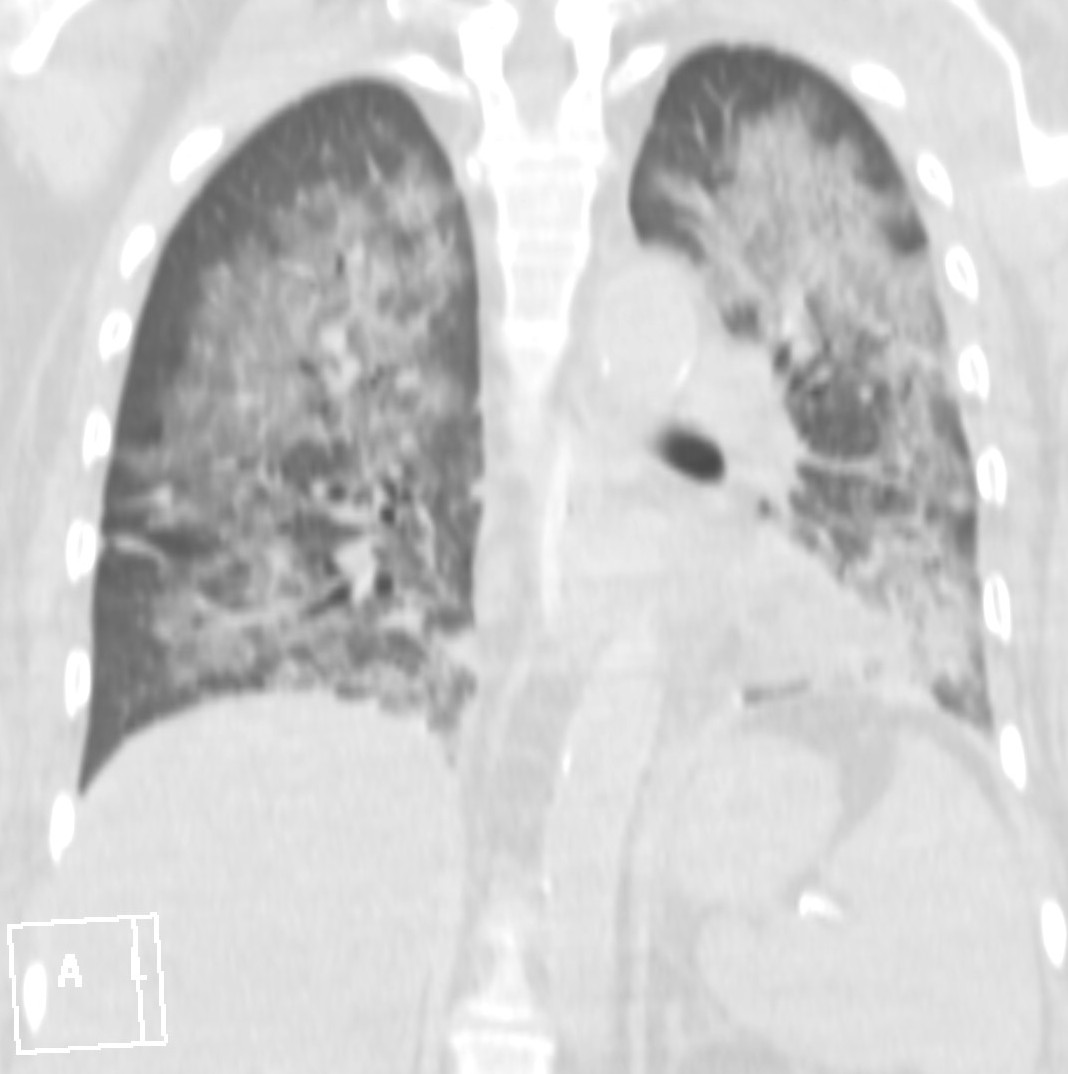

18. Tuberculosis a.) CT, b.) PA radiograph

45 year old man, pulmonary TB proven by microbiological culture.

LLL on CT: irregular, multicavitary nodular lesion: caverna.